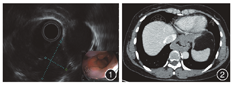

患者女,48岁,因"胸骨后不适6年余,加重半个月余"入院。患者于2013年外院胃镜检查发现食管距门齿35~38 cm右侧壁近后壁一3 cm×3 cm大小半球状隆起,同年在长海医院消化科行内镜超声检查,食管35~38 cm处右侧壁可见多发低回声团块。患者自觉不影响日常生活拒绝手术治疗。2019年10月,患者胸骨后不适感加重,于长海医院行内镜超声检查示食管下段多发低回声团块,相互融合,最大的两个大小分别为3.7 cm×1.7 cm、2.8 cm×1.7 cm,向腔内外突出,内部回声不均匀,平滑肌瘤可能(图1)。胸部CT检查:食管下段管壁外圈环形增厚,局部黏膜完整,局部管腔狭窄,增强后轻度较均匀强化(图2)。患者要求行内镜微创治疗。